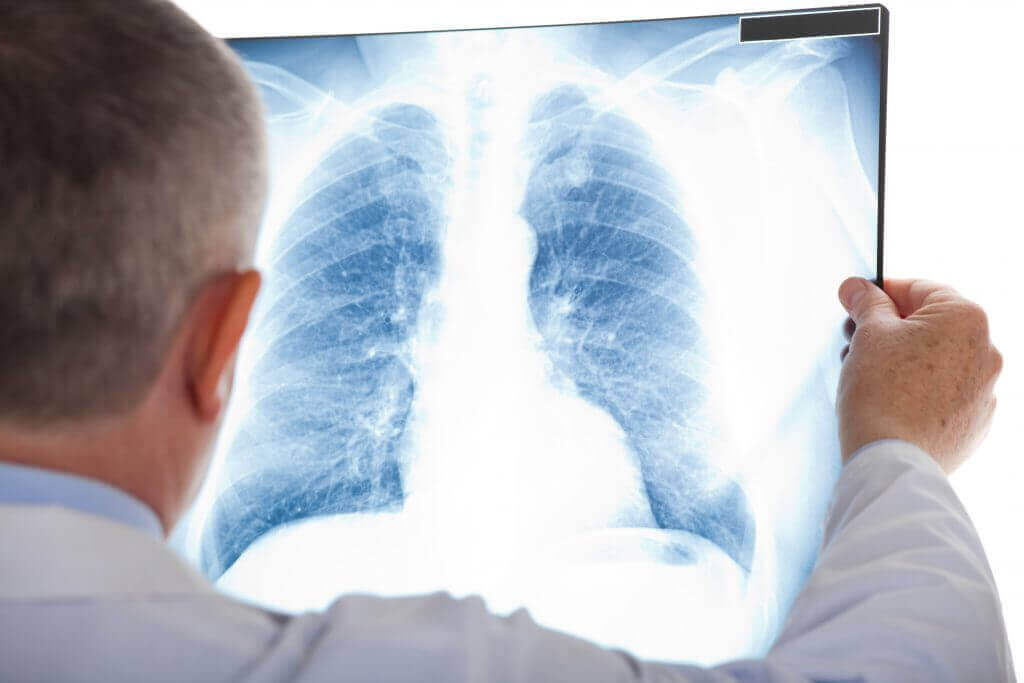

Om atelectase te diagnosticeren, is een gedegen klinische verkenning en een röntgenfoto meestal voldoende. Toch kunnen artsen een reeks technieken gebruiken om de diagnose te bevestigen of de ernst ervan te bepalen.

Deze technieken omvatten een CT-scan (computertomografie), bronchoscopie, echografie en oximetrie (Spaanse link). In feite maakt bronchoscopie het mogelijk om obstructies te observeren en zelfs blokkades op te heffen.

Om atelectase te diagnosticeren, is een gedegen klinische verkenning en een röntgenfoto meestal voldoende. Toch kunnen artsen een reeks technieken gebruiken om de diagnose te bevestigen of de ernst ervan te bepalen.

Deze technieken omvatten een CT-scan (computertomografie), bronchoscopie, echografie en oximetrie (Spaanse link). In feite maakt bronchoscopie het mogelijk om obstructies te observeren en zelfs blokkades op te heffen.